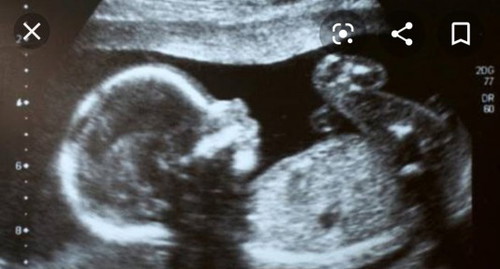

penyebab gerakan janin pasif

1. Kadar oksigen rendah 2. Usia kandungan 3. Air ketuban 4. Tidur 5. Kelahiran mati 6. Pertumbuhan janin terhambat 7. Posisi bayi 8. Placenta posterior Bundaku semoga bermanfaat ya, suka banyak yang nanya kenapa dedeknya kurang gerak atau kurang aktif.. Kalo kurang jelas ke dokter aja bundaa.. Be smart harus banyak baca dan searching2 ya bund, bisa lewat google youtobe dll...

sedang mengandung